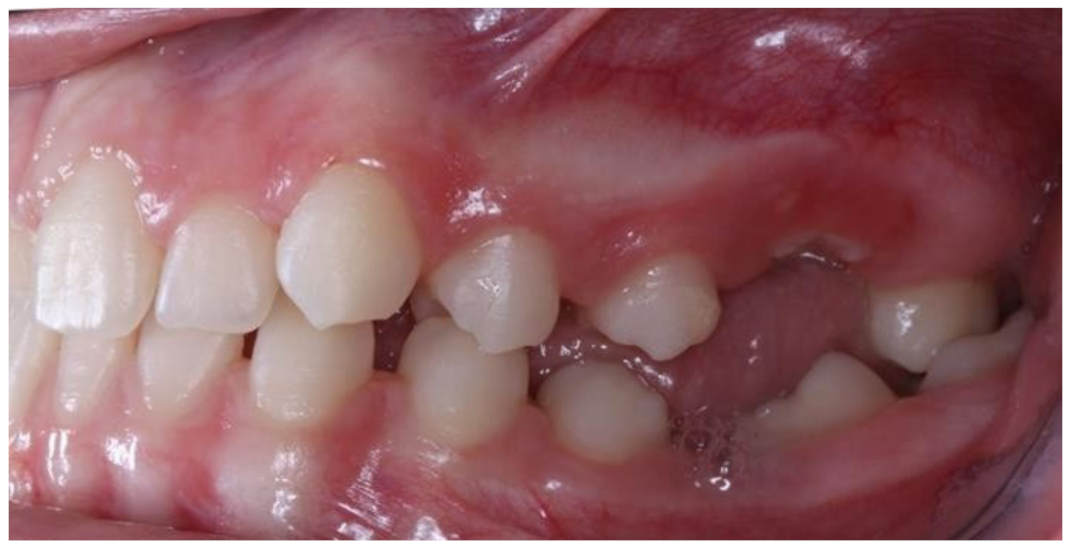

Figure 5.

Right photo of the female patient with PFE in bite relationship.

Open bite is present at the right posterior segment due to the impaction of the upper and lower left first molars.

Figure 5 and Figure 6 present a PFE case of a 17-year-old female patient referred to the Orthodontic Clinic of the Dental School of the National and Kapodistrian University of Athens, Greece. Clinical examination showed a posterior open bite on the right segment, as well as infraoccluded left upper and lower first molars. The patient’s orthopantomography shows no visible PDL of the right upper and lower first molars or the teeth distally related to them.